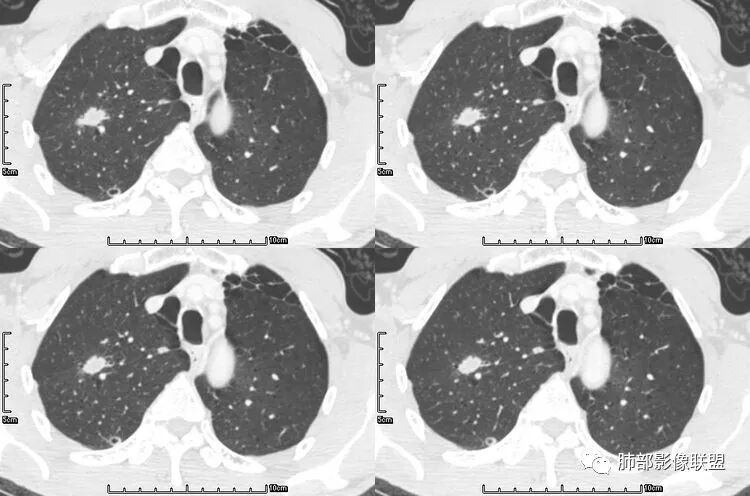

患者老年男性,咳嗽、咳痰、痰中带血伴胸闷2月余。长期大量吸烟史。查肝肾功能、血糖、血脂、心肌酶、电解质、血沉、C反应蛋白、抗“O”、类风湿因子、抗核抗体谱无明显异常。肿瘤标志物提示NSE、CYFRA21-1稍升高。胸部CT:肺气肿背景,左肺下叶后基底段不规则肿块影,见支气管截断,内见大片状低密度区及部分血管影,增强轻度强化,远端空洞形成。双肺多发不规则实性结节影、见毛刺、胸膜牵拉及血管集束,结节内见空洞形成,部分可见血管影,多位于胸膜下。双肺见多发肺大泡。综合考虑左下肺恶性病变并双肺转移。鳞癌或淋巴瘤可能。鉴别血管炎性病变及真菌感染。

张延军:双肺多发结节,空洞影,后者洞壁厚薄不均匀,部分腔内丝丝落落,呈分叶征,边缘见毛刺影,病灶大部分位于胸膜下,与血管相连,右肺下叶前基底段结节近段支气管截断,远端见空腔。左肺下叶病灶密度不均,背段支气管壁增厚,管腔狭窄。考虑1.双肺下叶占位性病变伴肺内空洞性转移 2.多原发的占位 3.肉芽肿性血管炎代排。

本病例左肺下叶肿块,有深分叶、毛刺、胸膜牵拉凹陷、支气管截断及纵隔内淋巴结肿大等征象,都均支持病灶为恶性,如腺癌,而且叶间裂的多发结节也提示是腺癌来源可能大;双肺多发结节、肿块,大部分病灶有分叶、毛刺及胸膜凹陷的恶性征象,与原发肿瘤本身的性质有关,所以应该与左肺下叶肿块同源,而且双肺多发病灶内空洞也具有多样性;